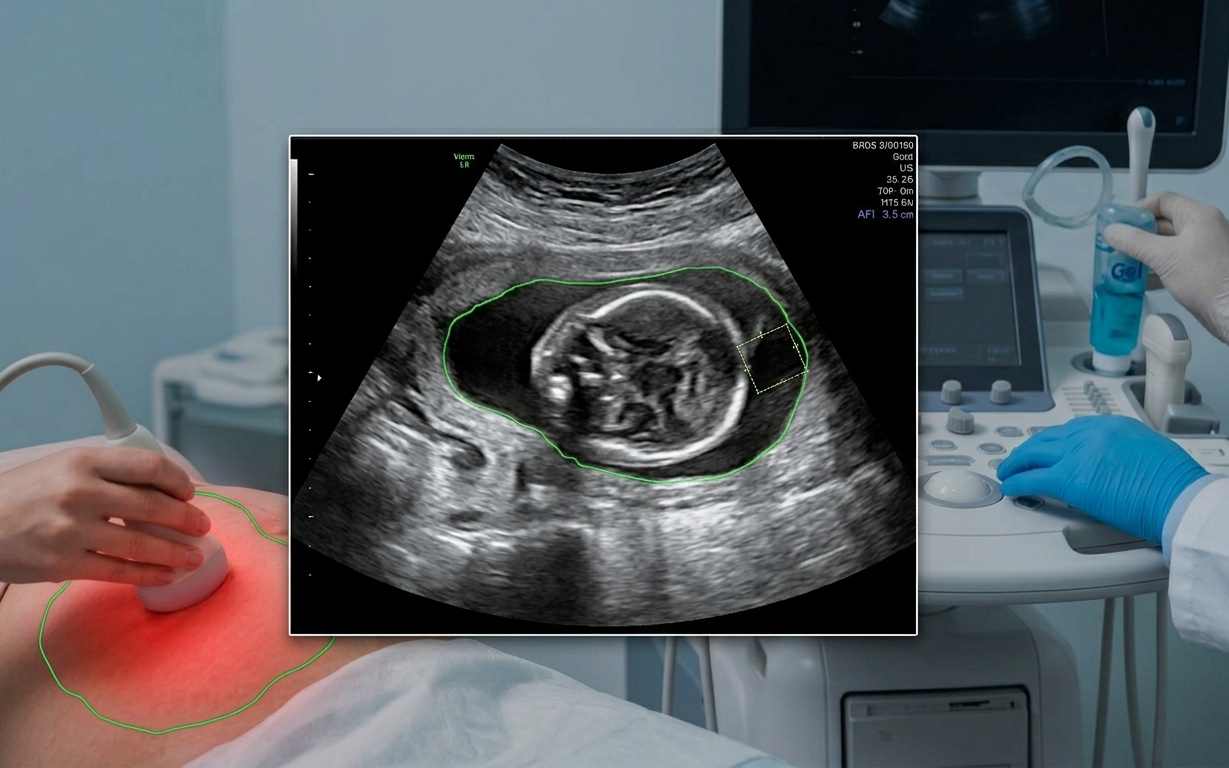

Thai kỳ ảnh hưởng đến tim mạch như thế nào?- Ảnh 1.

Các bác sĩ sẽ giám sát chặt chẽ sức khỏe tim mạch trong các buổi khám thai định kỳ.

Những điều chỉnh này là thiết yếu cho một thai kỳ khỏe mạnh nhưng việc theo dõi là rất quan trọng. Các bác sĩ sẽ giám sát chặt chẽ các chỉ số tim mạch trong các buổi khám thai định kỳ, cho dù mẹ bầu có bệnh lý tim mạch tiềm ẩn hay có nguy cơ gặp các vấn đề tim mạch liên quan đến thai kỳ.

Chăm sóc tiền sản giúp theo dõi sự tăng trưởng và phát triển của em bé nhưng đó cũng là cách tốt nhất để giám sát trái tim và sức khỏe tổng thể trong suốt thai kỳ. Bác sĩ sẽ theo dõi huyết áp mỗi lần khám và có thể yêu cầu xét nghiệm máu để giúp đánh giá các yếu tố nguy cơ, chẳng hạn như thiếu máu hoặc những thay đổi trao đổi chất ảnh hưởng đến sức khỏe tim mạch.